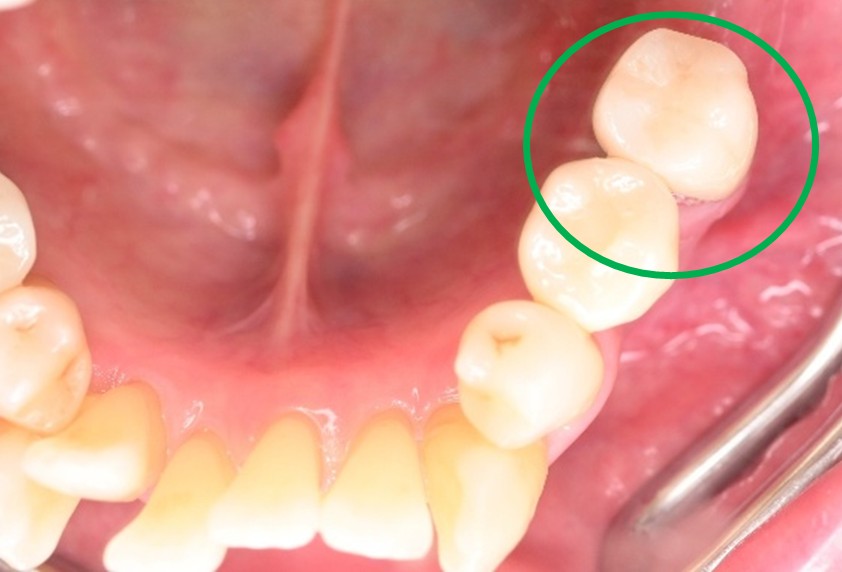

女性 Hさん 60代 (オールセラミック冠・インプラント)

主訴

右下のブリッジがゆらゆら動く。

治療内容

ブリッジの支台になっている奥の歯が、被せ物の中で虫歯になり、支台の役割を果たさず、前方の歯のみで支えられていました。前方の歯をそのままにして、後方の部分を切り離すと、そのまま取れてきました。中は、虫歯で歯根しか残っていない状況でした。この歯は、根管治療後、単独でオールセラミック冠を被せ、歯のないところにインプラントを埋入しました。

所感

今回の治療法には、次の3つの方法があります。

(1)虫歯になっていた歯の根管治療をし、土台を入れ、また再びブリッジにする。しかし、虫歯になっていたほうの歯は、ブリッジの支台として使うには、心もとなく長持ちしない可能性が高く、今度問題が生じたときには抜歯になる。

(2)虫歯になっていた歯に、単独で被せ物をし、歯のないところに1本だけの部分入れ歯を入れる。取り外しの入れ歯なので、自分の歯のような感覚で噛むことはできない。この方法も歯のない部分の負担を欠損の両側の歯に負担してもらうため、長持ちしない可能性が高い。

(3)虫歯になっていた歯に、単独で被せ物をし、歯のないところにインプラントを埋入する。欠損している部分の負担を前後の歯に負担させないので、歯を守ることができる。また、自分の歯と同じ感覚で食事をすることができる。

患者さんは、3つ目の方法を選択されました。一番長持ちし、これ以上歯を失わないためには、最良の方法だと考えます。

オールセラミック冠(失活歯):¥104,500(税込)

インプラント:¥363,000(税込)

合計:¥467,500(税込)

Before

冠の中で大きな虫歯になり支台の役割を果たしていませんでした。

【インプラント埋入前】

冠はブリッジを切断しただけで取れてきました。軟化象牙質を取り除いたところ、歯根しか残っていない状況で保存できるかどうかのぎりぎりのところでした。

After